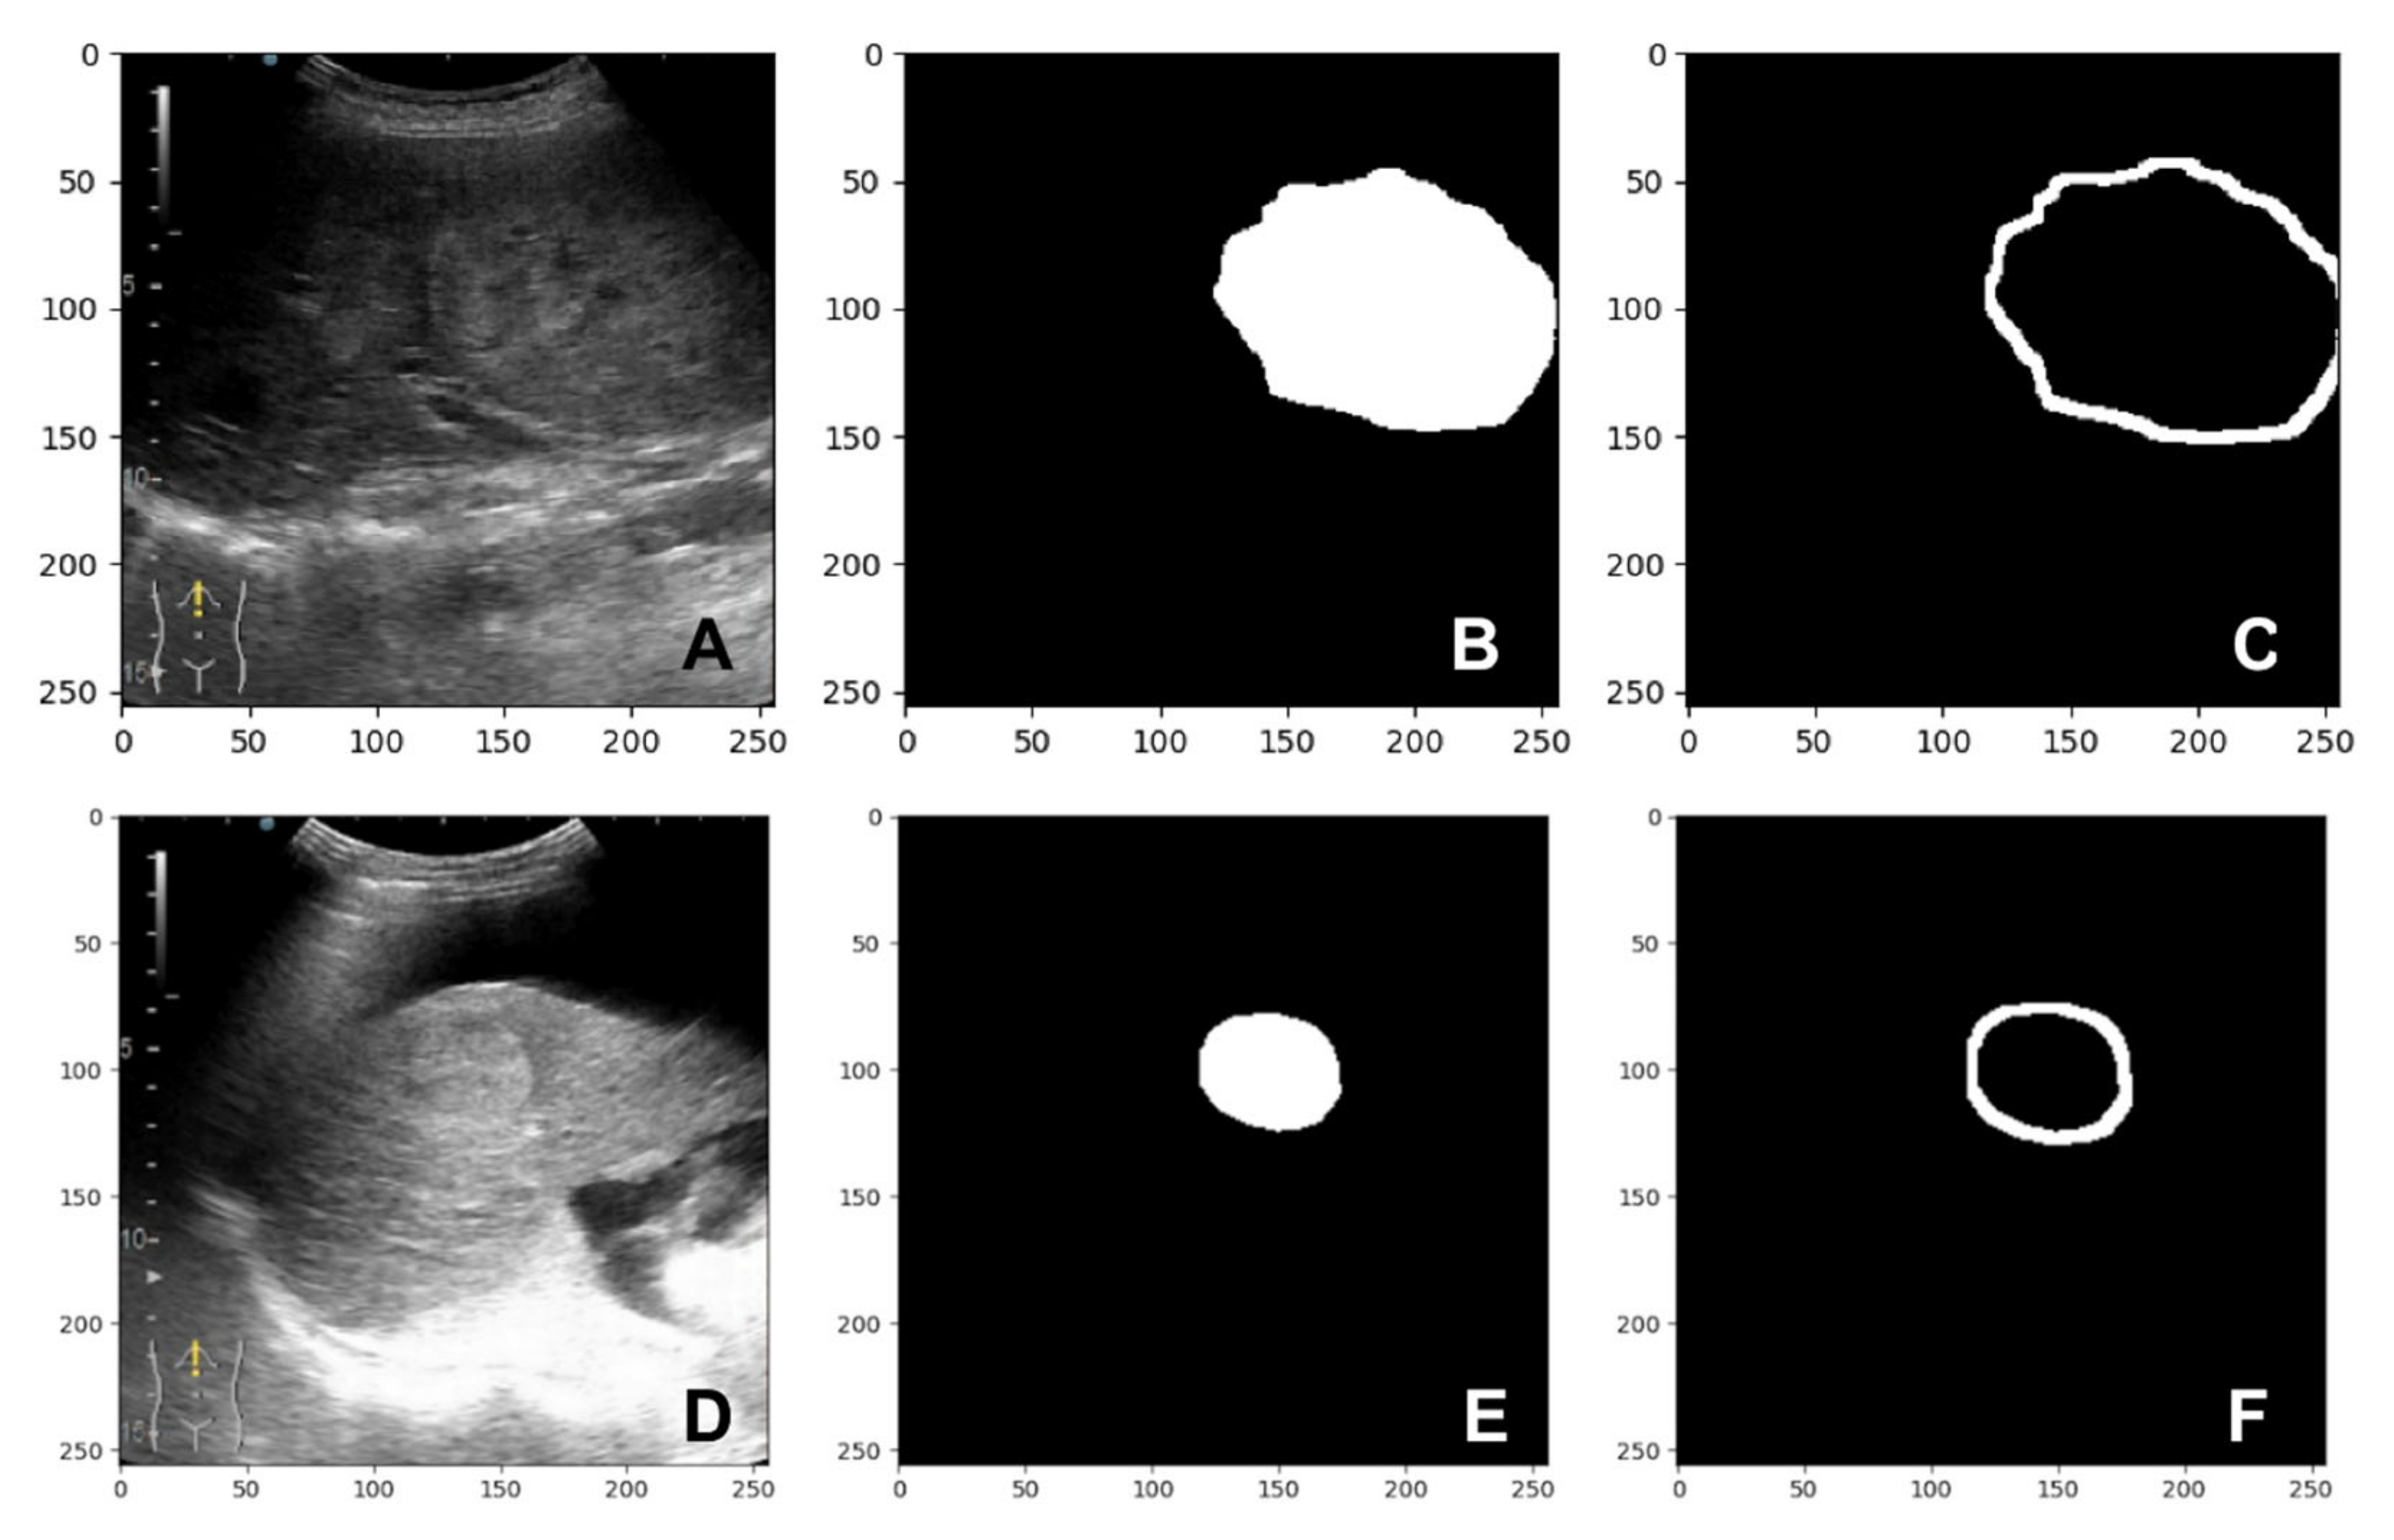

The U-Net [11] image segmentation model obtained from our previous work [10] was used to obtain region of interest for each frame in the video investigation file. By passing a frame from the ultrasound video investigation through the presented image segmentation model, a mask of 256 by 256 pixels is obtained. This mask can be further used to isolate the lesion from parenchyma in that specific video frame. Running a video investigation through the image segmentation model, the lesion is automatically isolated from the parenchyma, frame-by-frame, in the entire file; therefore, a time-intensity curve can be extracted from the investigation. A sample of inputs and outputs of the U-Net segmentation model are presented in Figure 2A–F.

Figure 2. Samples extracted from the image segmentation dataset: (A,D) B-mode frame cropped from the video investigation; (B,E) mask (label) created by the senior gastroenterologist; (C,F) the mask predicted by the segmentation model.